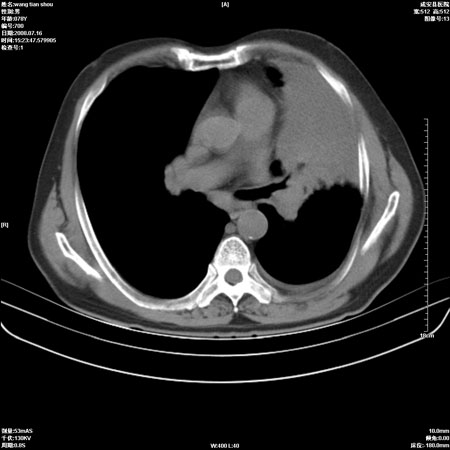

以下是引用qingjing在2008-7-16 19:55:00的发言:[br]1、左上肺不张并堵塞性炎症,建议支气管镜详查;[br]2、左侧胸腔少量积液。

以下是引用wzr在2008-7-16 20:26:00的发言:[br]左肺肺不张伴阻塞性肺炎!另:左侧胸腔少量积液。建议纤支镜检查!